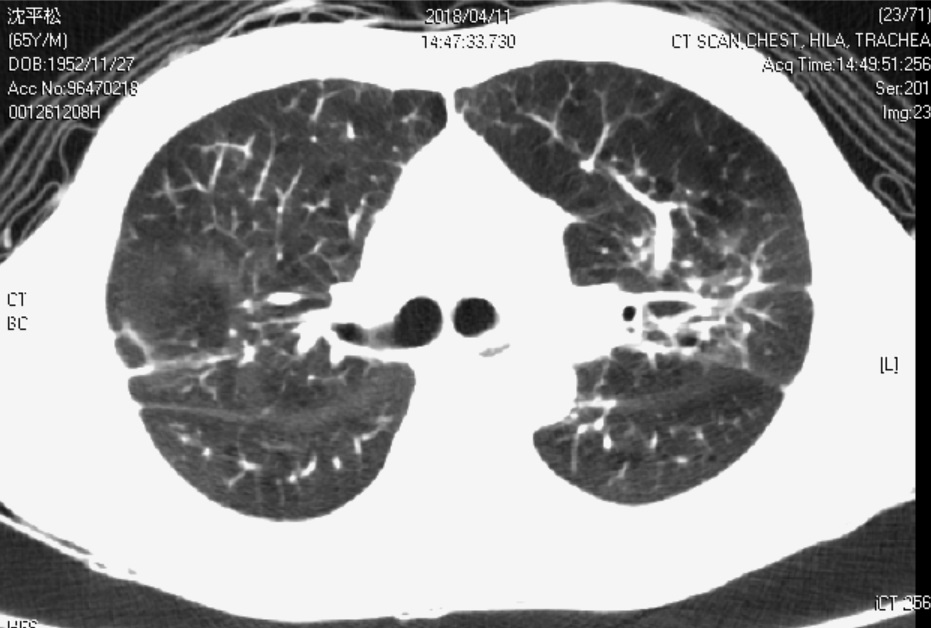

Figure 2. Chest CT image

Diffuse emphysema of both lungs with focal bronchiectasis and bronchial wall thickening is mentioned with peribronchial infiltrates and small peribronchial nodules(more obvious in RUL and LUL). The possibility of COPD with chronic bronchiolitis is more likely than lung to lung metastasis.

A solid mass 3cm is located in basal segment of RLL of lung with pleural retraction. Lung cancer can not be ruled out.